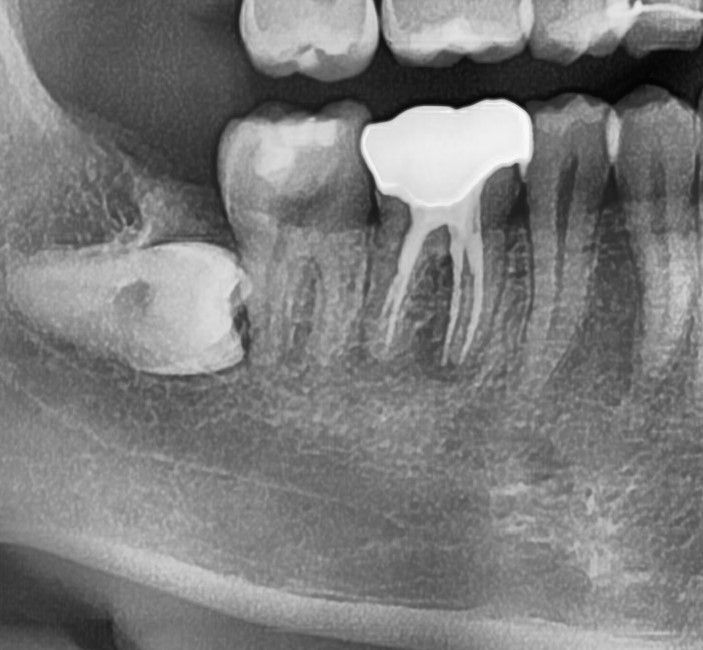

10년된 금니가 잇몸이 내려가서 속의 치아가 보이길래 병원가서 엑스레이를 찍었는데.

뿌리에 염증이 있는건가요? 열어서 교체하는게 좋을까요?

6번 치아의 뿌리 쪽에 방사선 상으로 염증 소견이 보입니다.

큰 불편감이 없다면 지켜볼 수 있지만 불편감이 있다면 재신경 치료가 필요할 수 있습니다.

네 사진상으로 근심뿌리쪽 염증잡혀있는 것 같습니다. 재신경치료 내지는 치근단절제술이 필요합니다.

근심측 크라운 하방도 마진이 아주 정밀하진 않아 하방 이차충치가 있을 수 있습니다.

그 뒤 어금니도 재평가가 필요합니다

사랑니의 경우 완전매복인데 옆 어금니에 아주 겹쳐 있지는 않아서 발치를 꼭 해야 할 필요까지는 없을 것 같으나 필요하다면 ct를 찍어보고 판단합니다.